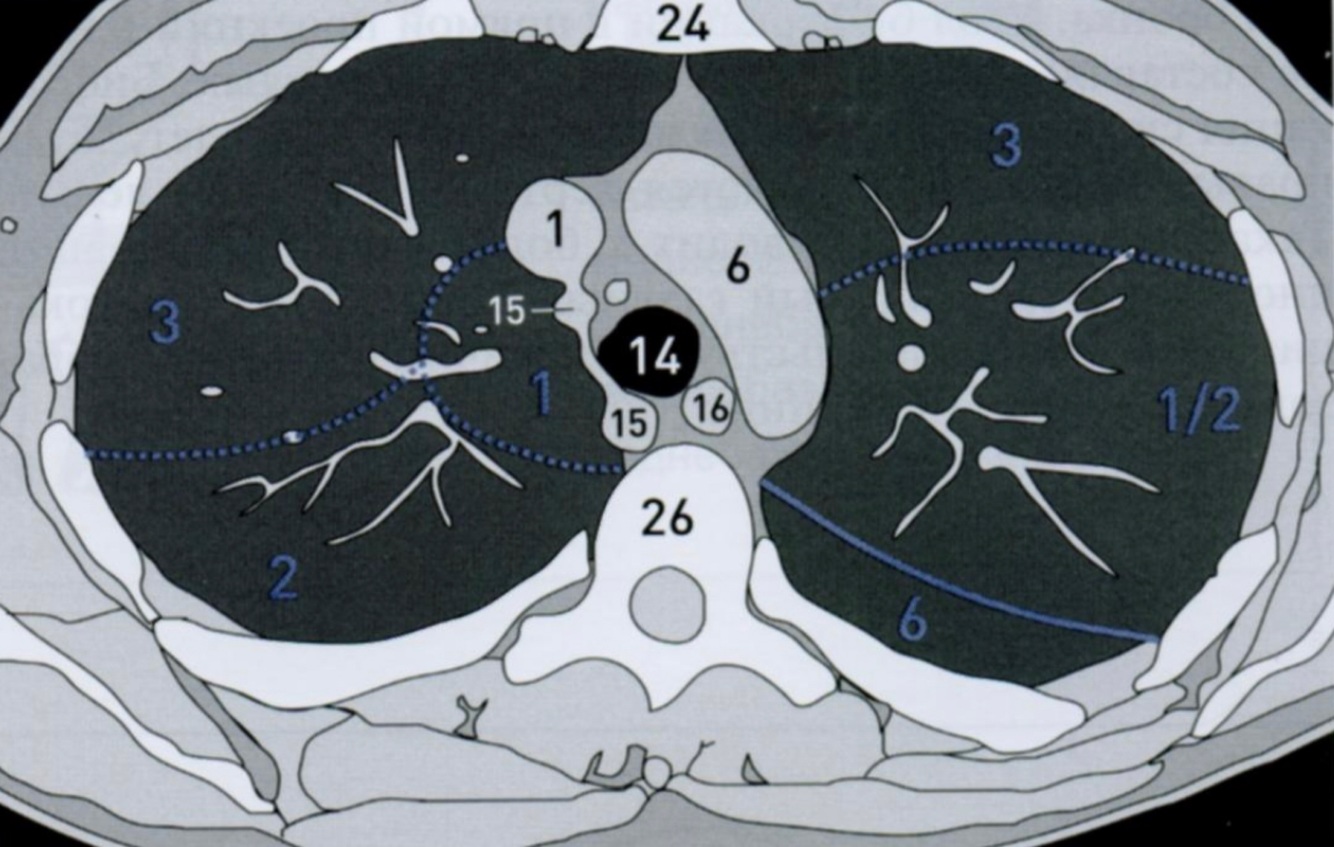

КТ грудной клетки №1

Назовите все анатомические структуры, которые Вы знаете, на данном КТ срезе (7).

Найдите грудину и грудные позвонки. Затем верхнюю полую вену, дугу аорты, трахею, непарную вену и пищевод.

A

24 - грудина

26 - грудные позвонки

1 - верхняя полая вена

6 - дуга аорты

14 - трахея

15 - непарная вена

16 - пищевод

Синим цветом отмечены номера сегментов.